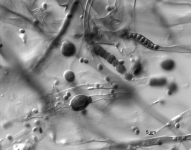

| Species Name: | Mucor circinelloides |

| Substrate: | ulcer on left calf, male 90 yr; biopsy + for hyphae with few septa and thick-walled yeast forms | Location: | USA Nebraska, Omaha, University of Nebraska Medical Center (GEO: 41.255,-95.976) |

| Characters: | CULTURE CONDITIONS no zygospores in matings with UAMH 8306 or 8307 - // HUMAN/ ANIMAL PATHOGEN primary cutaneous infection - Iwen PC, Sigler L, Freifeld AG, J Clin Microbiol 45:636-640, 2007 // MOLECULAR SYSTEMATICS ITS sequence comparison showed 99% similarity with GenBank sequence for Mucor circinelloides - (Click for publications citing UAMH 10385) |